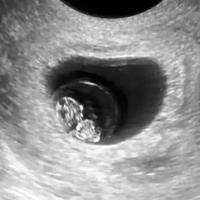

30天一超没胎芽胎心试管,可能是胚胎发育迟缓导致

在试管婴儿治疗过程中,移植后30天的第一次B超检查(简称"一超")是确认妊娠成功与否的重要节点。然而,当检查结果显示"未见胎芽胎心"时,许多准父母会陷入焦虑与困惑。这种情况在医学上被称为"空孕囊"或"胚胎停育",其发生率在试管婴儿治疗中约为15%-20%。本文将围绕"30天一超没胎芽胎心"这一现象,...